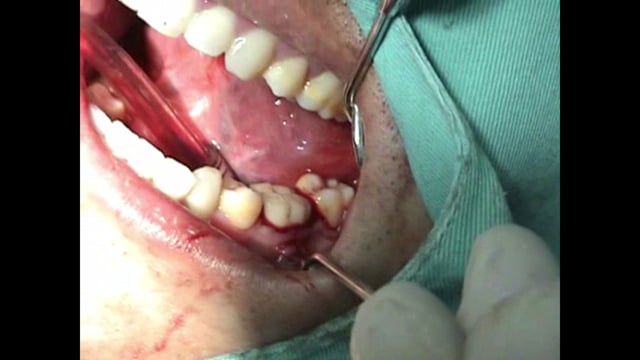

La técnica de reimplante intencionado post endodoncia ha caído en desuso en las últimas décadas. Esta técnica era recomendada cuando la apicectomía no era técnicamente posible. Se muestra un caso de reimplante intencionado en una molar mandibular. La técnica quirúrgica es descrita paso a paso señalando las limitaciones de su uso en la práctica clínica.